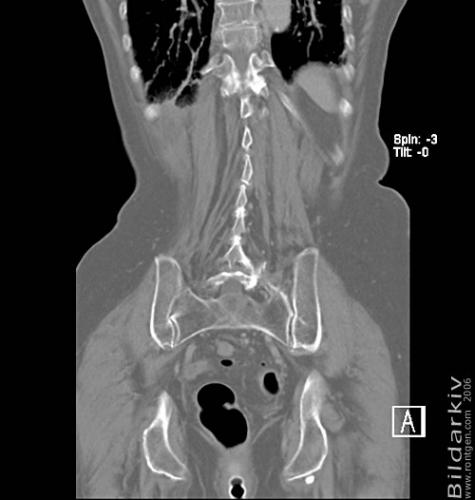

CT colon 41

Datortomografi av tjocktarmen (colon) med infunderad luft i tarmen samt med kontrast i blodbanan. Koronar bildserie.

CT multislice 16